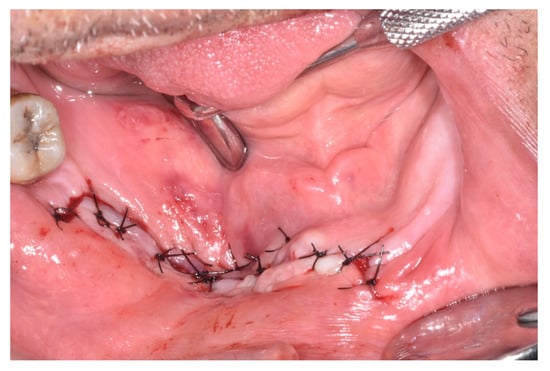

| Outcome | ||||||||

| Spontaneous expulsion of sequestrum | x | 1 | ||||||

| Healed | x | x | x | x | 4 | |||

| Progressive | x | 1 | ||||||